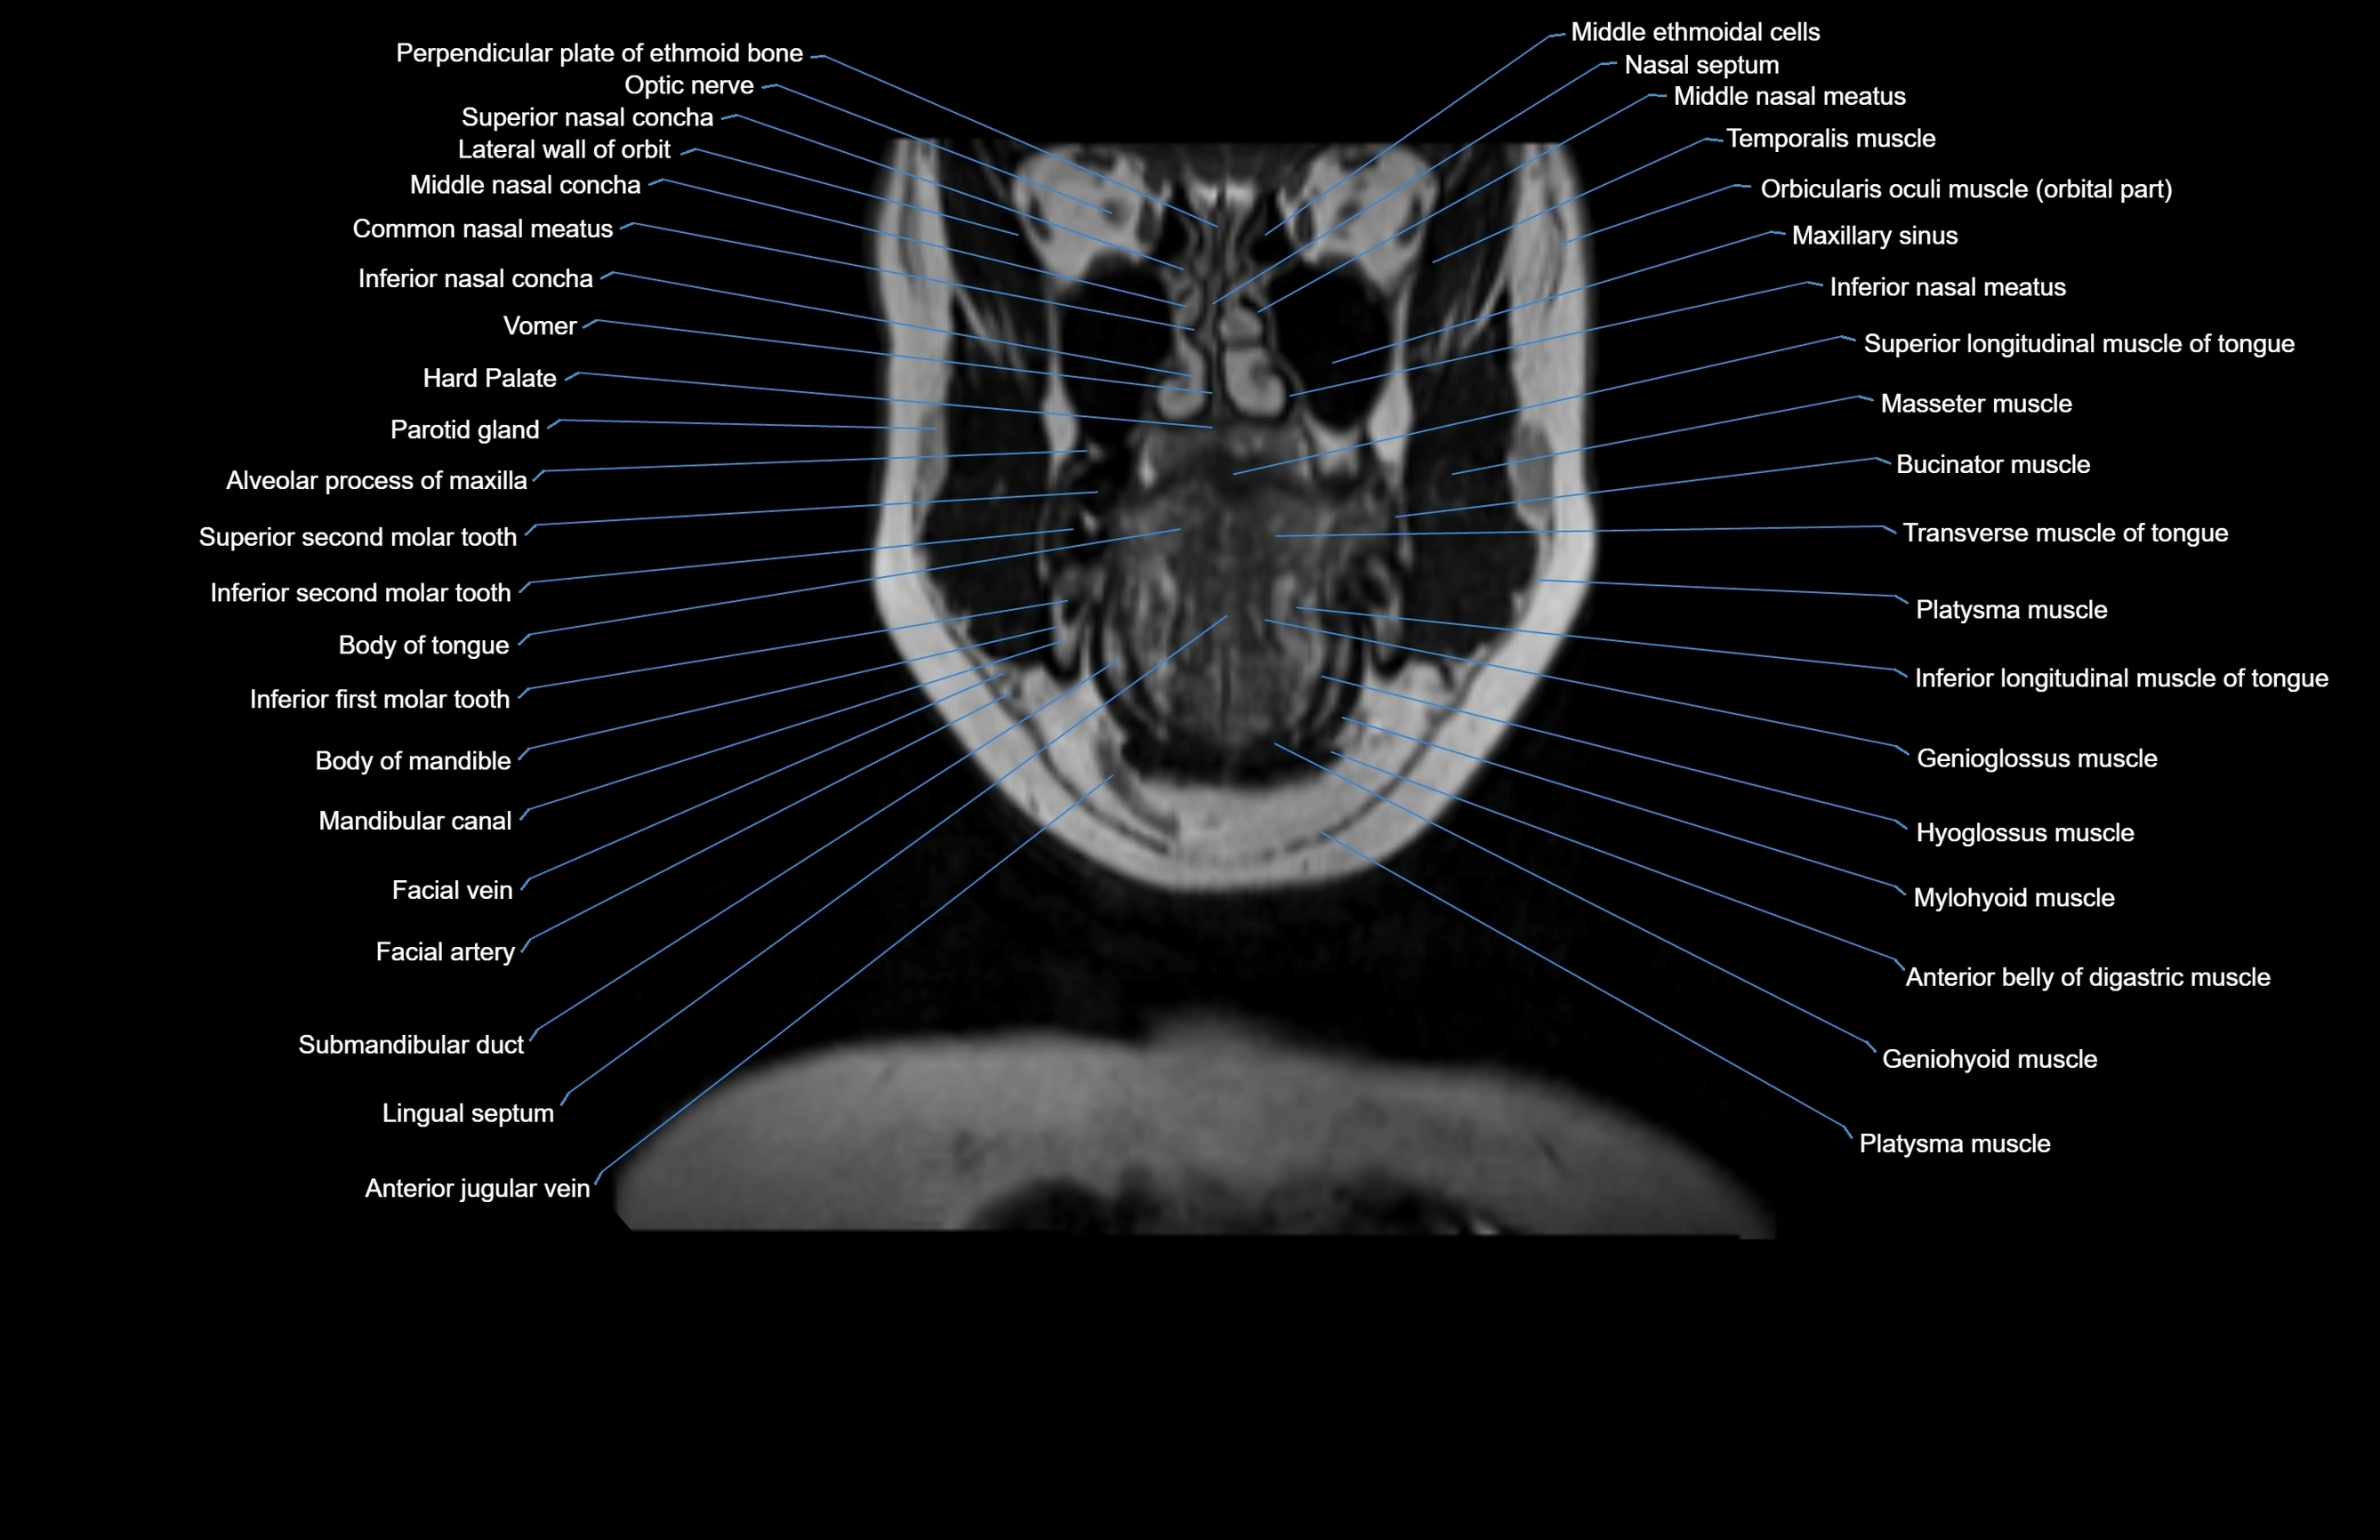

- Alveolar process of maxilla

- Body of mandible

- Body of tongue

- Common nasal meatus

- Hard palate

- Inferior nasal concha

- Inferior nasal meatus

- Mandibular canal

- Maxillary sinus

- Nasal septum

- Genioglossus muscle

- Hyoglossus muscle

- Mylohyoid muscle

- Anterior belly of digastric muscle